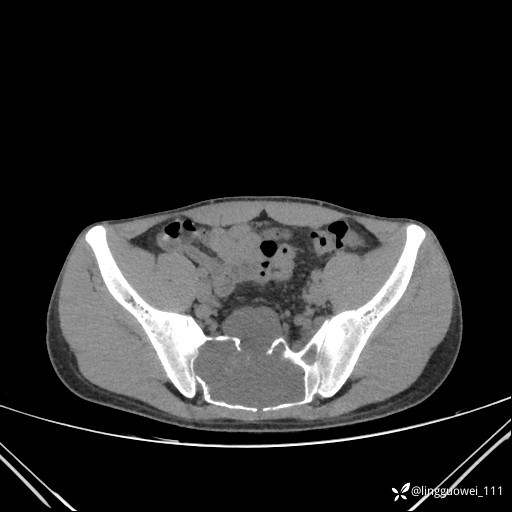

男,25岁,腰痛4年,加重左下肢痛5天,先上传X光片,第2天再上传CT。MR

MR:(忘记截图常规序列,不过应该不影响诊断)